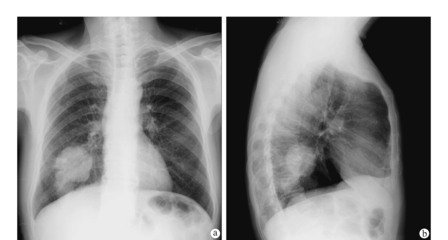

肺大疱一般继发于小支气管的炎性病变,如肺炎、肺结核或肺气肿。临床上常与肺气肿并存。因小支气管发生眼性病变后引起水中、狭窄,造成管腔部分阻塞,产生活门作用,使空气能进入肺泡而不易排除,致使肺泡内压力升高。炎症使肺组织损坏,肺泡间隔逐渐因泡内压力升高而破裂,肺泡互相融合形成大的含气囊腔。如果肺泡破裂后空气进入脏胸膜下间隙,则形成胸膜下大疱。肺大疱有单发也有多发。继发于肺炎或肺结核者常为单发或只有数个大疱,亦无明显肺气肿同时存在;继发于肺气肿者常为多发,表现为几个大疱伴有多个小疱,大疱周围的肺实质常伴有阻塞性肺部病变和肺气肿。肺大疱以位于肺尖部及肺上叶边缘多见。疱壁很薄,大小不一,数目不定。既可表现为宽基地座,亦可表现为狭颈体大的大疱。显微镜下可见疱壁为肺泡扁平上皮细胞,有时可仅有纤维膜或纤维结缔组织存在。

病人的症状主要与大疱的数目、大小以及是否伴有慢性弥漫性阻塞性肺部疾病密切相关。较小的、数目小的单纯肺大疱可无任何症状,有时只是在x线检查时或因其他疾病作剖胸术时偶被发现。体积大或多发性肺大疱可有胸闷、气短等症状。当肺大疱病人突然发生气急、咳嗽、呼吸困难、或有与心绞痛相似的胸痛;体格检查有发绀,气管向健侧移位,患侧叩诊呈鼓音,听诊呼吸音消失时,应疑有大疱破裂并形成自发性气胸。肺大疱继发感染少见,亦很少并发咯血,主要并发症是自发性气胸或血气胸。

1.自发性气胸肺大疱可以没有任何症状。在突然用力,如剧烈咳嗽、提重物或体育运动时压力突然增加,肺大疱破裂,气体自肺内进入胸膜腔,形成自发性气胸时,可能出现呼吸困难,气急、心慌,脉搏加快等,气胸使胸膜腔负压消失,气体压缩肺组织使其向肺门部萎陷,萎陷的程度取决于进入胸腔的气体的多少,以及肺及胸膜原有病变的病理情况,进入胸腔的气体量大,肺组织原有病变轻,顺应性尚好的,肺萎陷较多,有时可达到一侧胸腔的90%,气体迅速进入胸腔,肺组织急速萎缩,则症状严重,甚至有发绀。如果患者除肺大疱以外,尚合并有肺气肿、肺纤维化、肺组织长期慢性感染等病变,肺大疱破裂时虽然有一部分气体进入胸腔,而肺组织萎陷程度可以较轻,但因为患者原有肺功能已减退,症状也较重。X线可见被压缩的肺形成的气胸线,如果有粘连存在,则气胸线不规则。肺大疱破裂后,其中一小部分裂口较小,肺组织萎缩后裂口自行闭合,漏气停止,胸腔积气逐渐吸收,胸腔负压恢复,肺复张痊愈。

2.张力性气胸若肺大疱破裂后形成活瓣,吸气时胸腔负压增高,气体进入胸腔,呼气时活瓣关闭,气体不能排出,尤其是咳嗽时,声门关闭气道压力增高,气体进入胸腔,声门开放后,气道压力减低,裂口又闭合,每一次呼吸和咳嗽都使胸腔内气体量增加,就形成张力性气胸。张力性气胸时患侧肺组织完全萎缩,纵隔被推向健侧,在健侧肺组织亦被压缩的同时心脏大血管移位,大静脉扭曲变形,影响血液回流,造成呼吸循环严重障碍,患者可出现呼吸困难、脉快、血压下降,甚至窒息、休克。患侧胸廓隆起,多伴有患侧皮下气肿,气管明显向健侧移位,病情危重,常需要急诊处理。

3.自发性血胸肺大疱引起的自发性血胸,多数由肺尖部的大疱或大疱周围的肺组织与胸顶粘连及粘连撕裂活动出血。粘连带中的小动脉直径可达0.2cm,血管起源于体循环,压力较高,同时胸腔内是负压,更增加了出血的倾向。另外,由于肺、心脏、膈肌运动的去纤维化作用,胸腔内的血液不凝固,因此出血很难自动停止。临床症状可因出血的快慢而不同,出血缓慢时,患者可表现为逐渐加重的胸闷,呼吸困难,X线可见膈角变钝,或胸腔积液的抛物线影像。出血迅速时,短期内可以有休克表现。